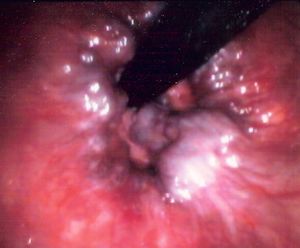

هناك نوعان من البواسير الشرجية داخلية وخارجية.

1- البواسير الداخلية: تنشأ داخل القناة الشرجية في الغشاء المخاطي وهي توسعات وعائية في نهاية الأوعية الباسورية، تتبارز بشكل كتلة صغيرة داخل الشرج، قد تتدلى تدريجياً نحو الأسفل فتصبح البواسير داخلية وخارجية في آن واحد.

2- البواسير الخارجية: وتشاهد عند فوهة الشرج وتكون مغطاة عادة بالجلد، مما يجعلها شديدة الألم وتضم إحدى مجموعتين:

- حادة مؤلمة: وهي بواسير خارجية متخثرة بشكل ورم دموي تحت الجلد يظهر عند فوهة الشرج ويبدو بشكل حبة صغيرة زرقاء اللون شديدة الألم.

- مزمنة: وهي حليمات حارسة جلدية شرجية غير مؤلمة وهي شائعة جداً.

البواسير الداخلية

تظهر أهم أعراض البواسير الداخلية [2] عند رؤية قطرات أو نقاط دم أحمر متقطعة عند عملة التغوط (التبرز)، والمشكلة هنا هي أن الدم يظهر في أغلب الأحيان دون شعور المريض بالألم، ولهذا السبب غالباً يتعرف مريض البواسير الداخلية[3] علي مرضه في وقت متأخر من الإصابة بحيث تكون البواسير ممتلئة بالدم وتكون جلطة، أو في بعض حالات البواسير الداخلية عندما تكون البواسير قريبة من فتحة الشرج.